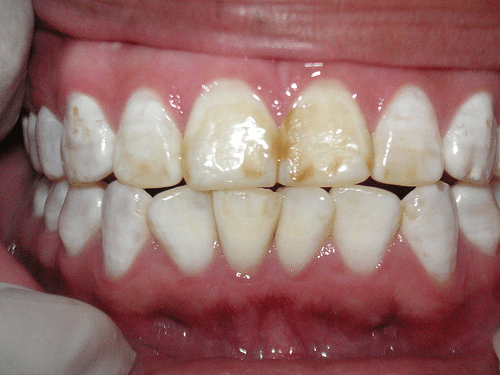

Tandfluorose is een aandoening die ontstaat door te veel fluoride en uit zich in witte of bruine vlekken op het tandglazuur.

In ernstige gevallen kan dit leiden tot broze tanden. Dit illustreert het eerste aspect van het gevaar van fluoride: wat bedoeld is als bescherming, kan bij overmaat juist schadelijk zijn.